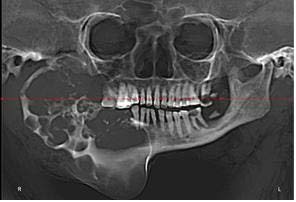

Figura 2: A - Computed tomography 3D reconstruction image of a patient with extensive Ameloblastoma; B- Virtual surgical planning

Ameloblastoma Treatment (Fig6): Two mandibular resections and reconstructions with titanium plates were performed to remove extensive tumors while preserving jaw functionality.

Figure 6: Computed tomography image of a patient with extensive ameloblastoma